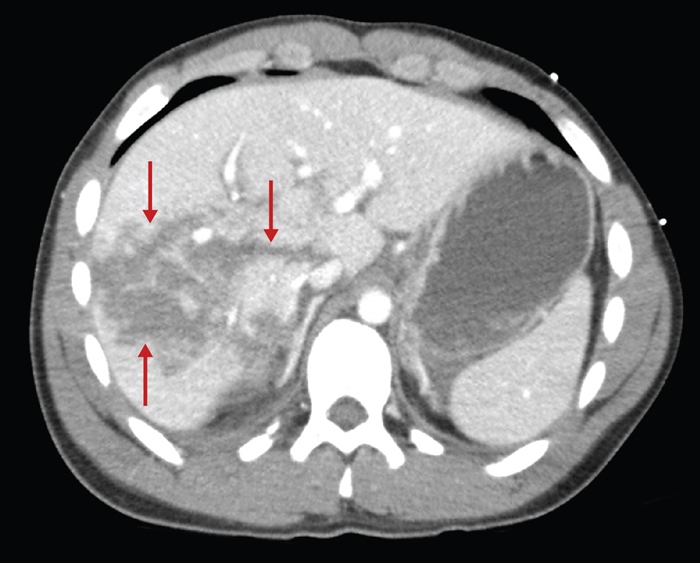

The liver and spleen are at high-risk for injury during blunt abdominal trauma.

CT scan of the abdomen gives detailed information about the pathology and source of hemorrhage (if present). It may also assist in planning of operative intervention.